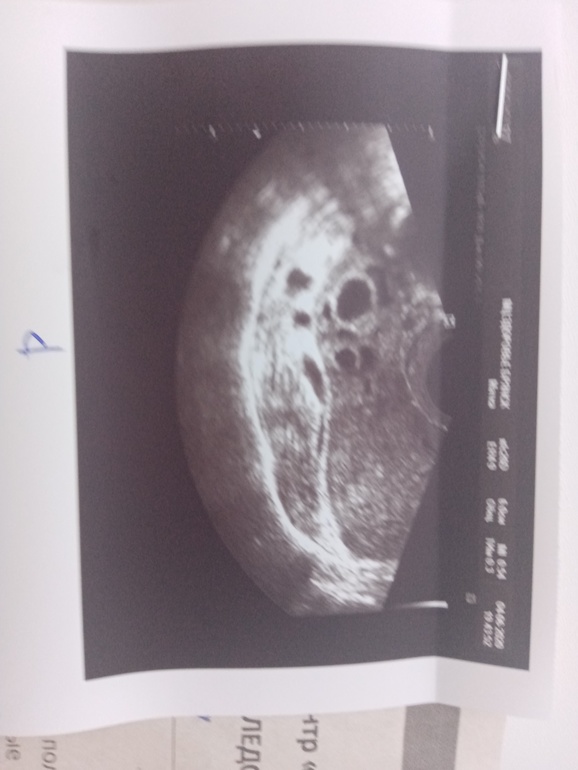

Сегодня попала наконец на узи.

УЗИ прилагаю, жду помощи

Когда-то у меня была киста, я пила вовнутрь таблетки рассасывающие все эти вещи и свечи противовоспалительные ставила. Но там киста была гипоэхогенная, после нелопнувшего фолликула. А сейчас непонятно что.